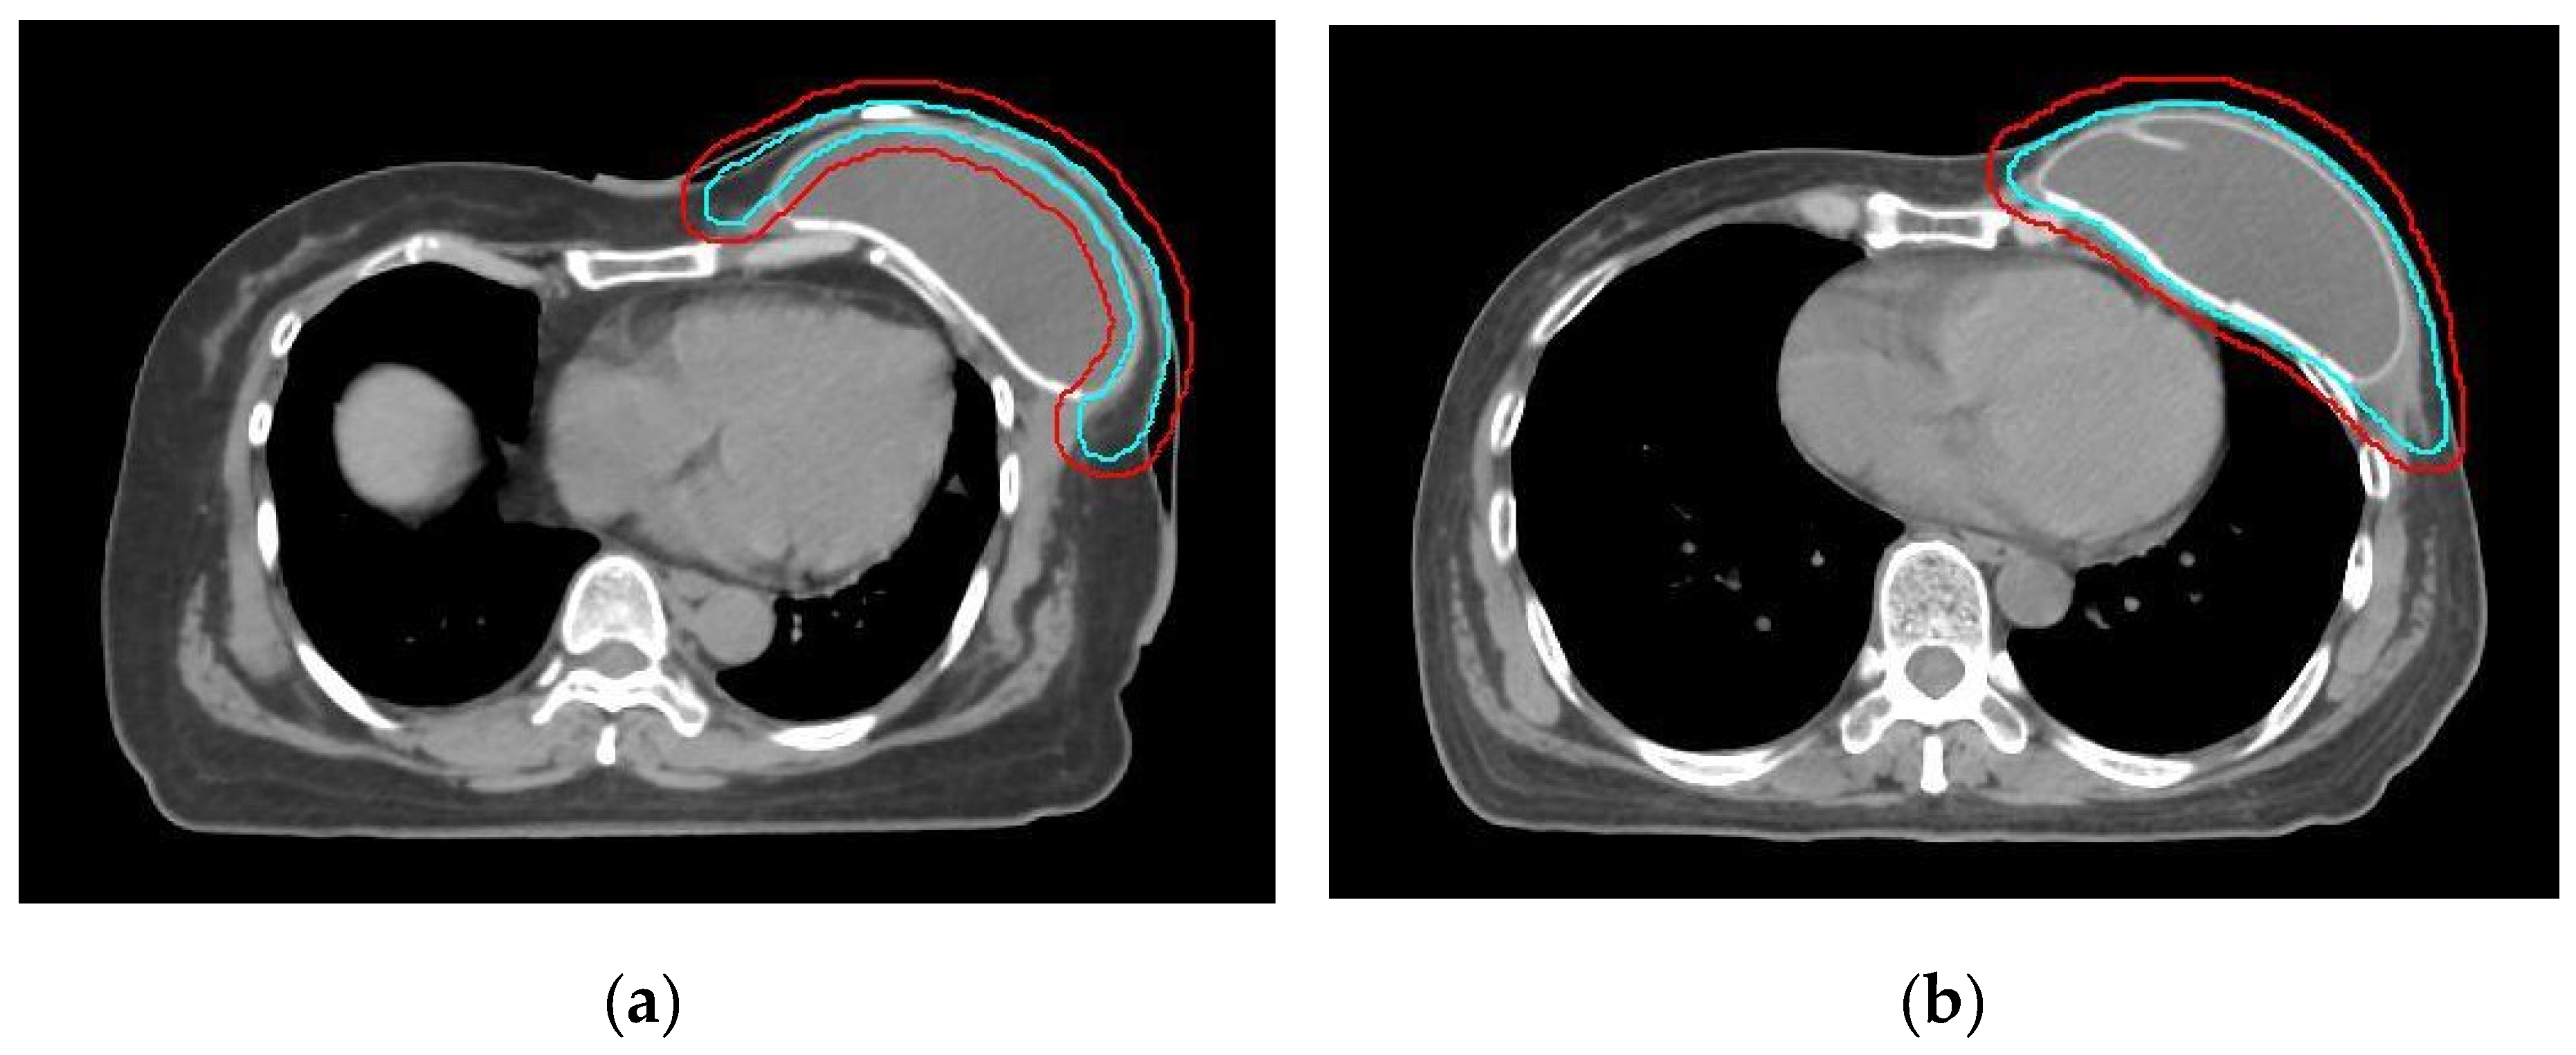

| RT technique | 0.61 | ||

| Hybrid+IMRT | 3 (2+1) | 1 (0+1) | |

| VMAT+Helical tomotherapy | 12 (8+4) | 10 (5+5) | |